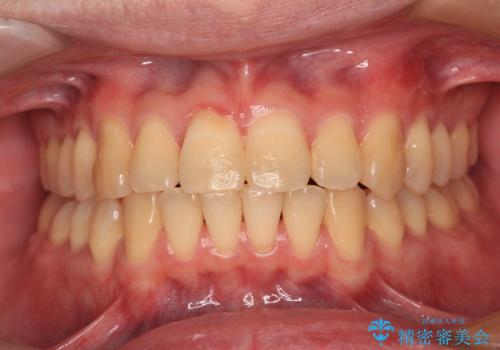

受け口傾向の咬み合わせ 前歯のデコボコをワイヤー矯正で素早く改善

- 前歯の見た目を気にして来院された患者様です。

ワイヤー矯正でもマウスピース矯正でも対応可能とお伝えし、非常に悩まれていましたが、2年後に転勤の可能性が高いとのことで、治療終了までの期間を想定しやすいワイヤー矯正にて治療を行うこととしました。

前歯のクロスバイトは、改善の途中で歯髄壊死を起こすリスクが高くなるため、マウスピース矯正よりもワイヤー矯正をお勧めしております。

この患者様もクロスバイトはあっという間に改善され、1年強で速やかに治療を終えることができました。